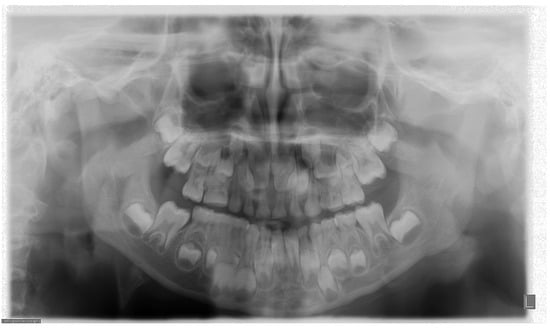

3. The Variables of a Correct PAN Examination

4. Frequency of Errors in PAN Performance and Interpretation